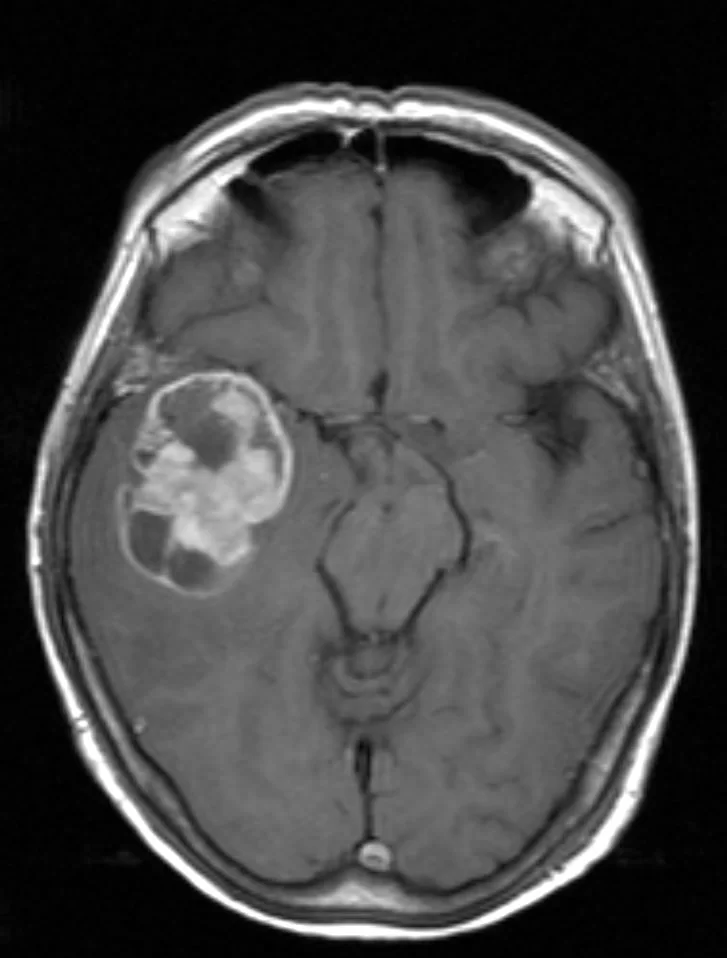

Η μαγνητική τομογραφία ανέδειξε ευμεγέθη χωροκατακτητική εξεργασία δεξιά κροταφικά με σημαντικό περιεστιακό οίδημα, ύποπτη για κακόηθες γλοίωμα.

Διενεργήθη δεξιά κροταφική κρανιοτομία και πλήρης εξαίρεση της βλάβης με τη βοήθεια νευροπλοήγησης, διεγχειρητικού υπερήχου αλλά κυρίως με τη χρήση 5-ALA ανοσοφθορισμού.

Η μετεγχειρητική μαγνητική τομογραφία εγκεφάλου (substraction sequences) δείχνει πλήρη αφαίρεση της βλάβης. Η ιστολογική εξέταση ανέδειξε γλοιοβλάστωμα (IDH1/2 mutant, MGMT neg).